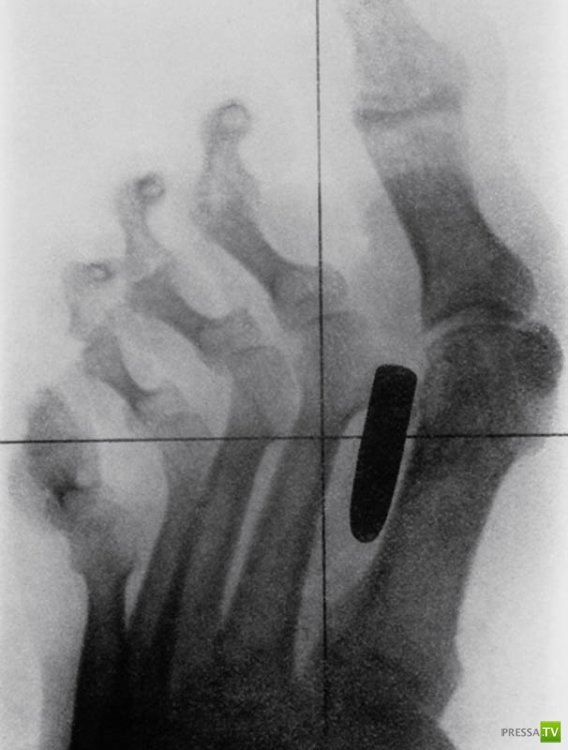

Старинный рентгеновский снимок ступни солдата англо-бурской войны (1899-1902) с огнестрельным ранением. Пуля застряла между большим и вторым пальцами.